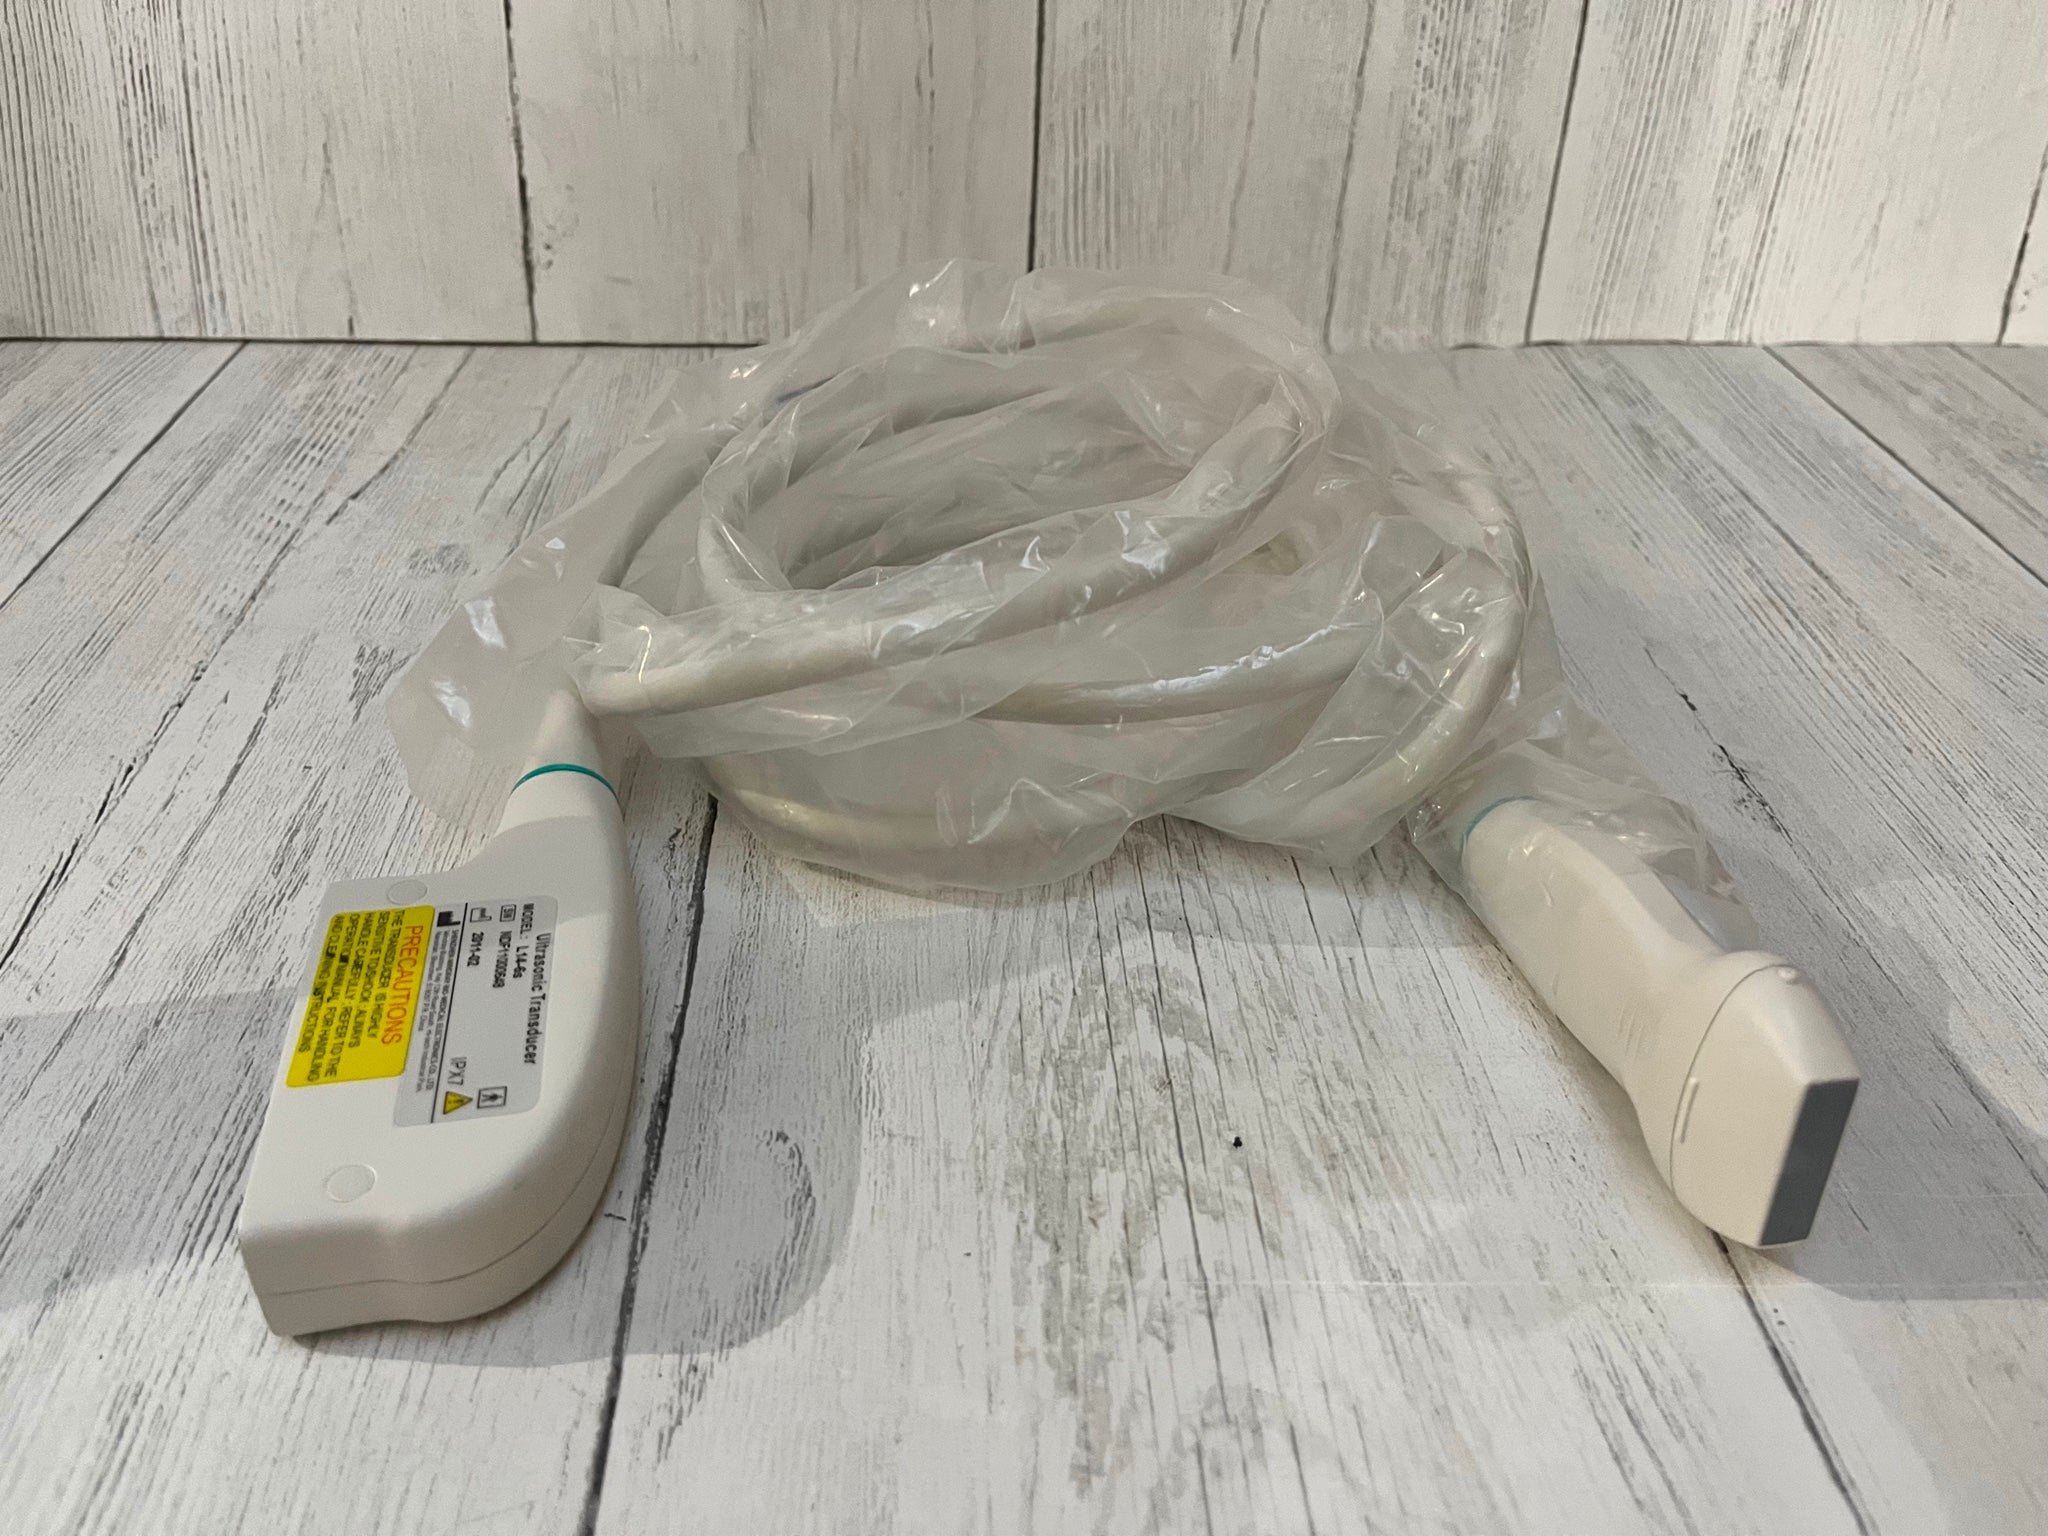

The Laptop Color Doppler Ultrasound is an innovative diagnostic machine designed for clear and precise imaging. It boasts advanced features, making it an indispensable tool for medical professionals. Whether you're in a hospital setting or a small clinic, this portable ultrasound scanner provides accurate diagnostics without compromising on quality.

One of the key features of the Laptop Color Doppler Ultrasound is its portability. This means you can easily transport it between examination rooms or even take it off-site when necessary. Despite its compact size, it offers robust capabilities that rival larger, stationary units. Medical professionals appreciate the balance of convenience and high performance it offers.